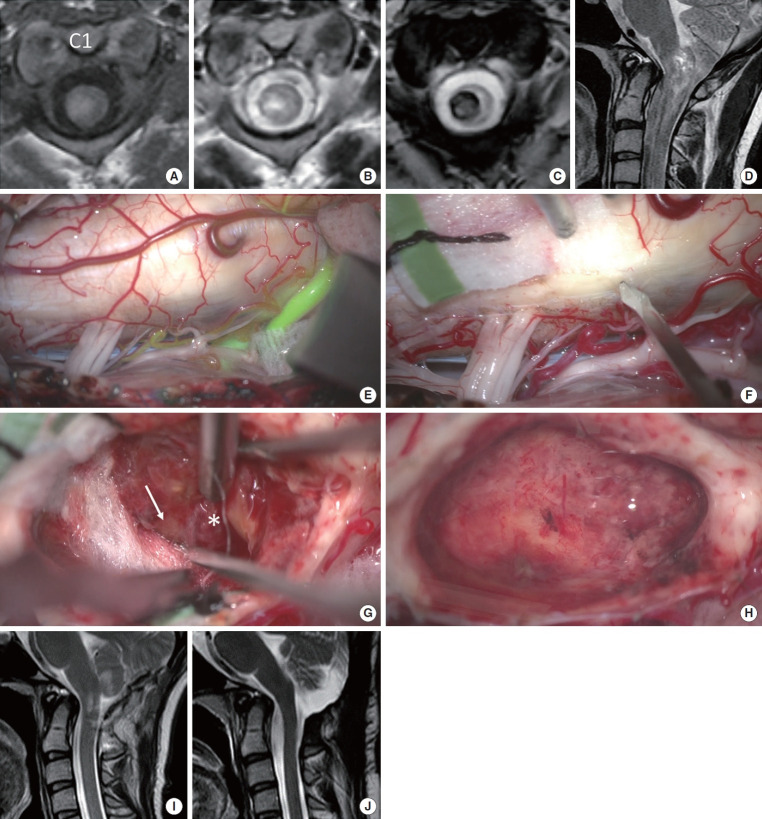

目的:髓内出血(IH)合并高颈海绵状畸形(CM)仍然是神经外科医生面临的一个重大挑战。本研究旨在评估后外侧沟(PLS)入路治疗这些复杂病例的有效性和安全性。方法:本单中心回顾性研究包括近4年来58例经手术治疗的脊髓髓内肿瘤。在IH侧采用PLS入路切除CM。术前、术后一周及最近随访时采用改良的McCormick功能量表(MMCS)评估神经功能。结果:从数据库中确定了6例伴有C3水平以上CM的IH患者。平均年龄31.2岁,女性4例。术前症状持续时间为0 ~ 48个月。所有6例患者均实现了CM的完全切除,未发生包括呼吸系统并发症在内的严重不良事件。平均随访时间为21.7个月。术前MMCS平均评分为3.0分,术后早期维持在2.5分,最近一次随访进一步提高到2.2分。1例腹侧型CM患者在初次手术后30个月在同一水平再次出血。该患者随后接受了第二次手术,采用前外侧沟入路,耐受性良好。结论:PLS入路即使在高颈椎处也能安全切除CM。然而,腹侧型CMs仍然是外科关注的主要问题。

Results: Six patients with IH associated with CM above the C3 level were identified from the database. The mean age was 31.2 years, and 4 of the 6 patients were female. Symptom duration prior to surgery ranged from 0 to 48 months. Total removal of the CM was achieved in all 6 cases without any serious adverse events including respiratory complications. The average follow-up duration was 21.7 months. The mean MMCS score was 3.0 before surgery, maintained at 2.5 in the early postoperative period, and improved further to 2.2 at the most recent follow-up. One patient of ventral-type CM experienced recurrent hemorrhage at the same level 30 months after the initial surgery. This patient subsequently underwent a second surgery using the anterolateral sulcus approach, which was well tolerated.